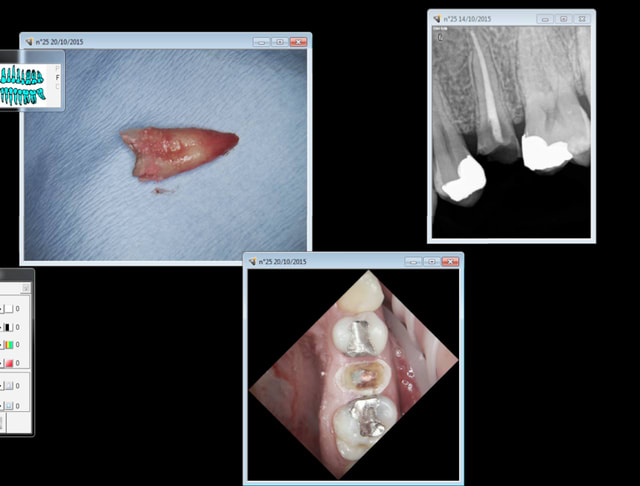

caries 17, 15 + 25 à virer :

1. para apicale 25

2. quick sleeper palais entre 16-15

3. amg 17 15

4. ext 25

20 mn.

Mais c'est qu'il nous fait une dentisterie de grand papa le chicot ! -))))

Tarif de merde soins de merde ( mais ca va quand meme tenir 30 ans je pense) C'est ca ou faire des tarifs de prothèse hors de prix pour rattraper le déficit des compos sous digue.